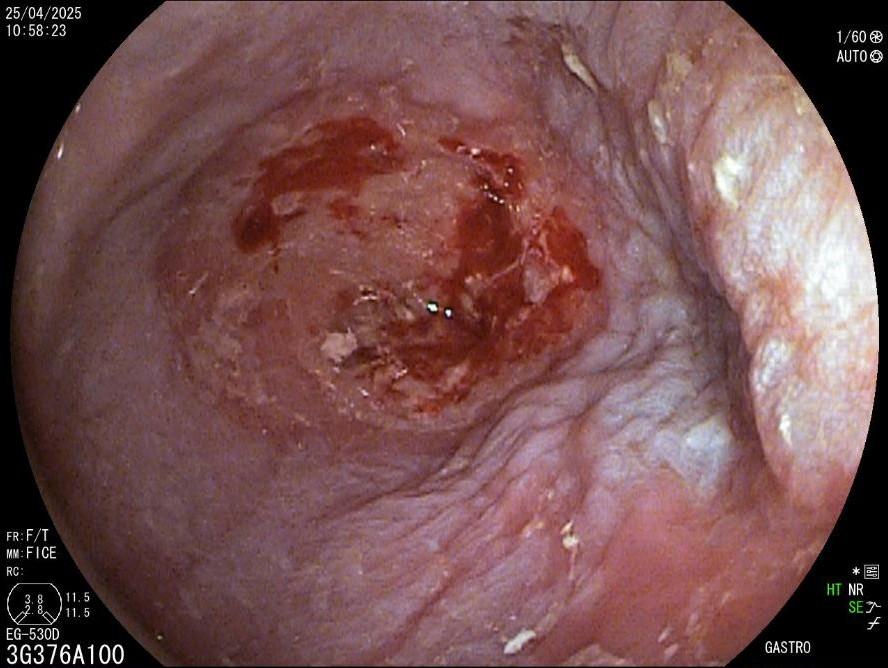

La evaluación endoscópica reveló un divertículo de Zenker de 3 cm, con retención significativa y acumulación de saliva y restos de comida (fig. 1). Se consideró que el paciente no era apto para la cirugía y se planificó una septotomía endoscópica.